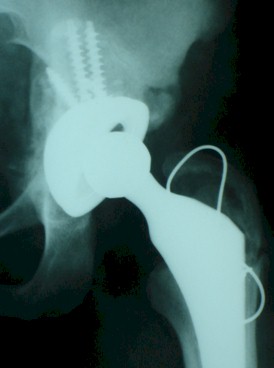

Se retiraron los componentes femoral y acetabular observándose en defecto óseo de aproximadamente 3 centímetros de diámetro producido por la cabeza, se rellena con injerto óseo de banco de hueso (01 cabeza femoral) se decide colocar prótesis de revisión de la casa Piemca modular tallo largo no cementado y se fija el acetábulo con 3 tornillos comprimiendo el injerto óseo. (Foto 3) y se retiran tres tornillos proximales de la placa en diáfisis femoral por la longitud del vástago (Foto 4) (Foto 5)

Foto 3.